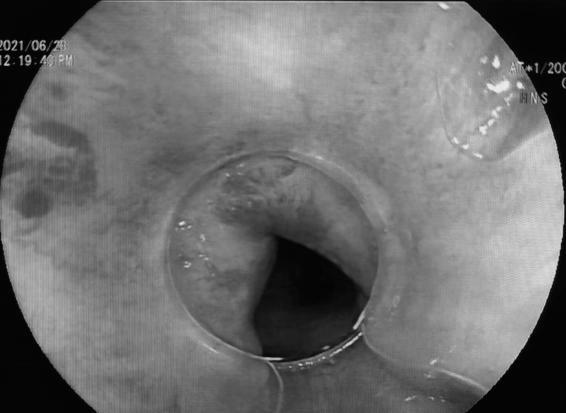

术前内镜下直肠曲张静脉

术后内镜下直肠曲张静脉